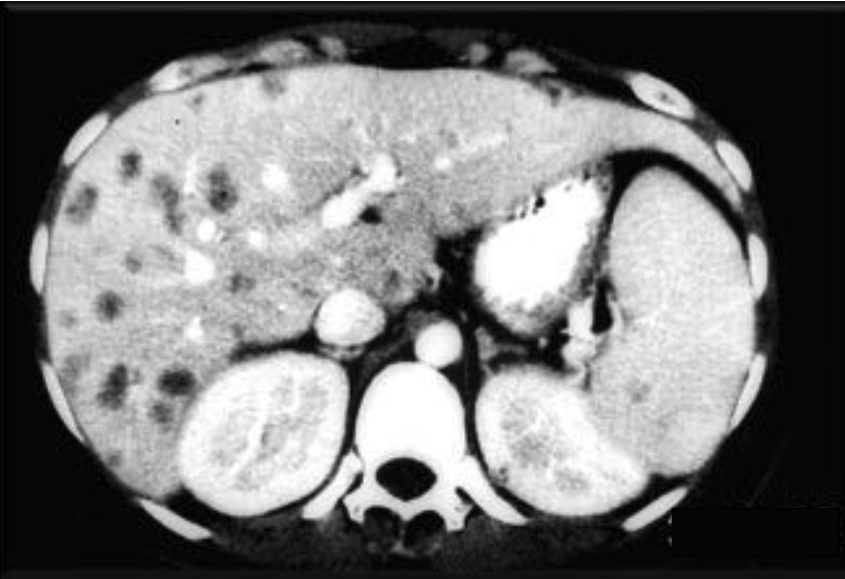

- Hepatosplenic candidiasis (chronic disseminated): Fever, elevated alkaline phosphatase, target lesions on imaging

Tissue diagnosis of invasive candidiasis relies on special stains to highlight fungal elements in tissue specimens:

| Stain | Appearance |

|---|---|

| PAS (Periodic Acid–Schiff) | Magenta yeast and pseudohyphae |

| GMS (Gomori Methenamine Silver) | Black yeast and hyphae against green background |